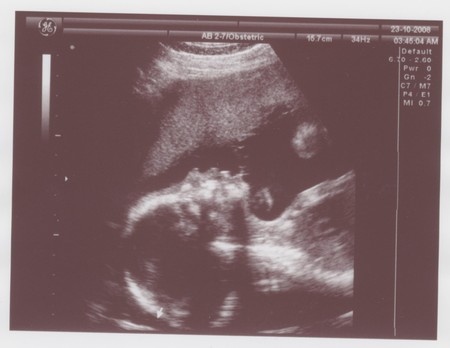

Фото сладкого сынульки!

Вот он.. мой лапочка! Носик точно достался от папки) и ножки длинные)

боже, какое чудо!!! Точно в папу носиком ))) Класс)))У меня зайка вообще личиком на папу похожа )))